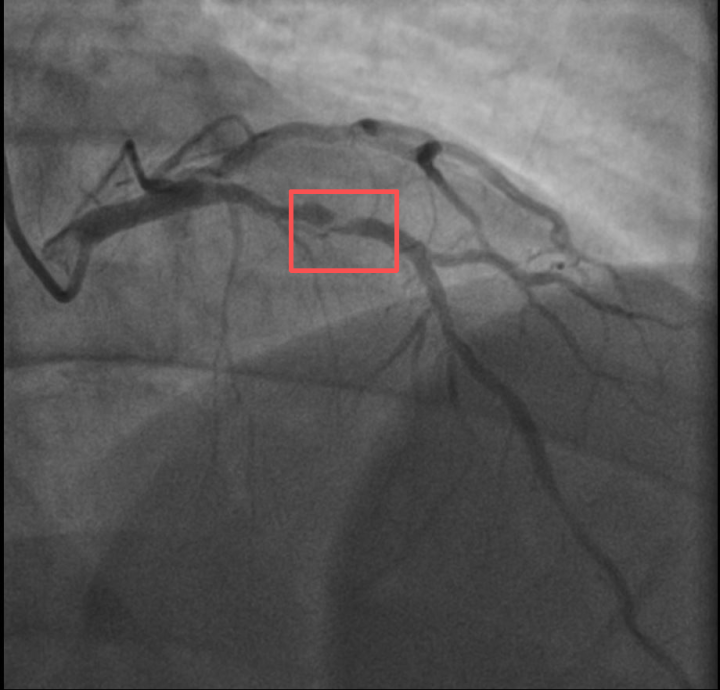

前不久,他带孩子到羽毛球场操练,手痒之下自己也上场挥杆,仅10分钟左右,就因心前区剧烈绞痛被送进了急诊。浙江医院心血管内科副主任汤益民主任医师分析,剧烈运动导致这位患者心脏的不稳定斑块破裂,进而造成前降支近段次全闭塞。所幸送医及时,接受紧急介入治疗后,孙先生的身体险情被成功化解。

介入治疗前后影像图